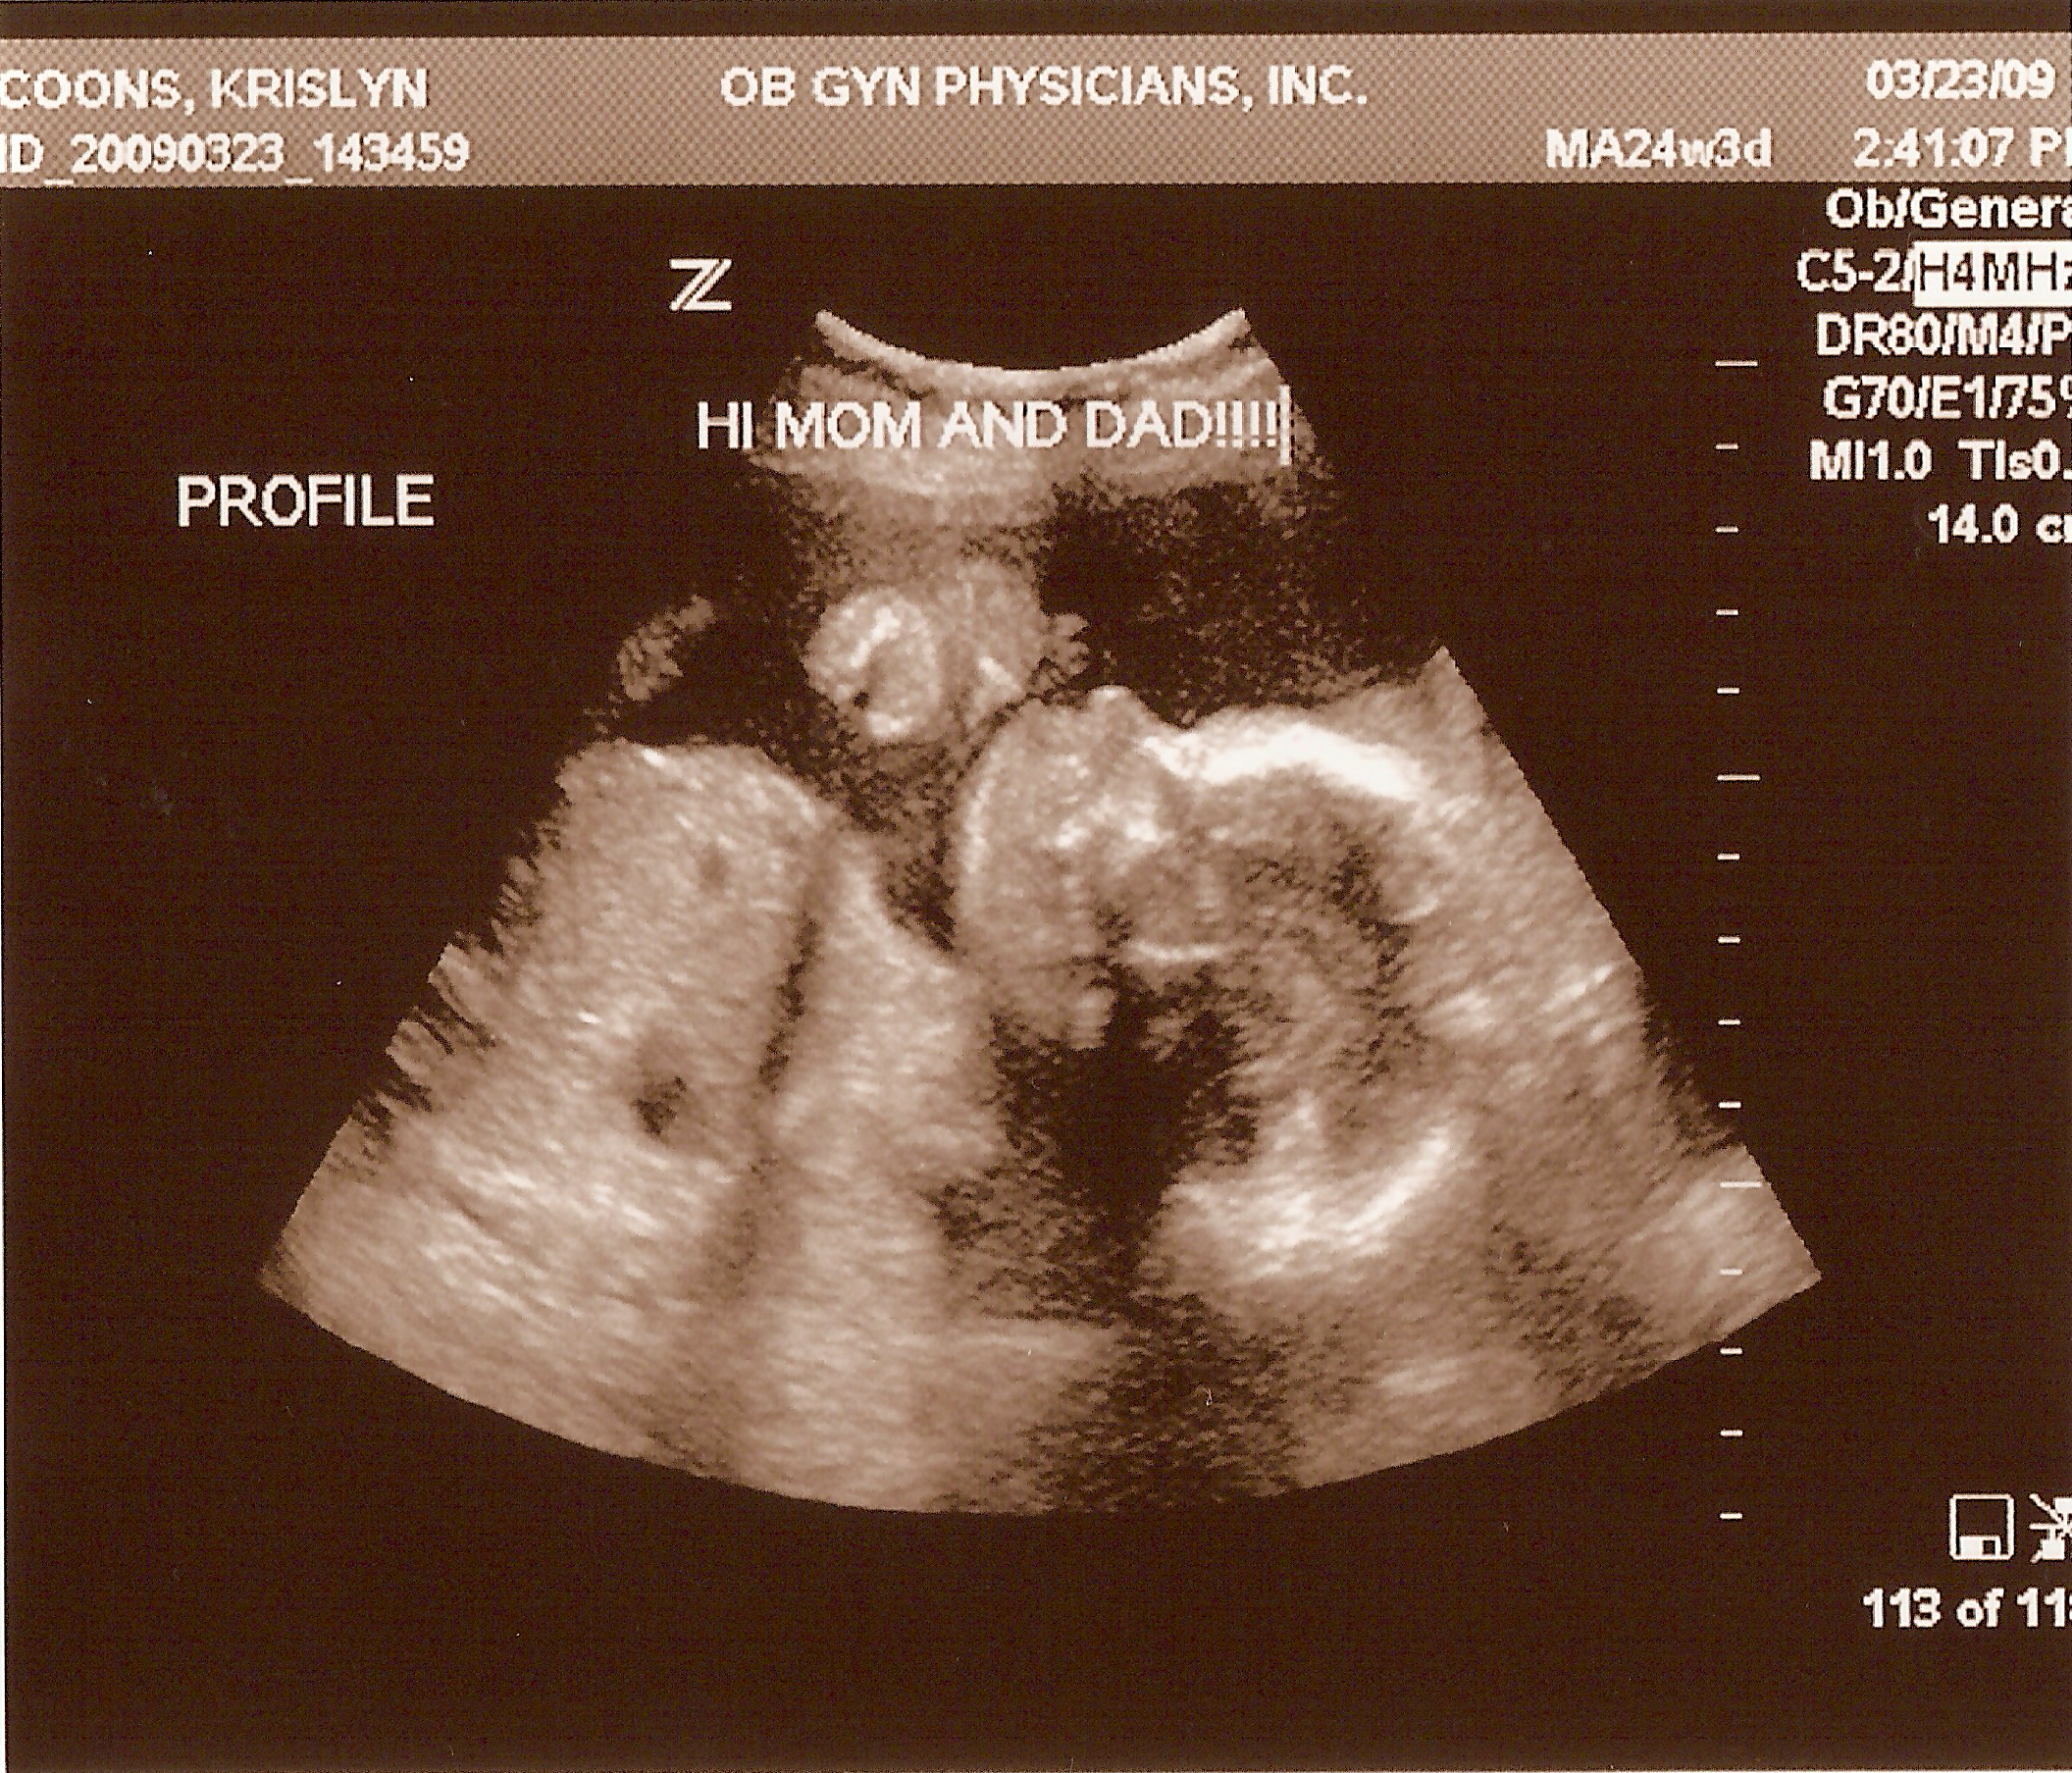

24 weeks

Second ultrasound! Baby is doing well and all measurements checked out--weighing in around 1.7 pounds. No abnormalities on the PentaScan, so no need for an amnio. And Krislyn is really starting to show now!